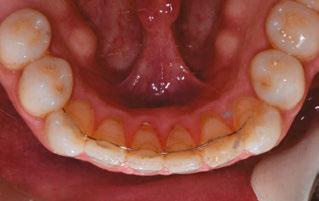

Figure 2: Initial lower occlusal

This case involves a 13-year-old female patient with a complex malocclusion that includes multiple dental and skeletal issues. During the initial consultation, clinical evaluation showed severe maxillary crowding along with generalized spacing in the mandibular arch. The patient’s occlusal relationships were asymmetric, with a Class I molar relationship on the right side and a Class II molar relationship on the left. Notably, an anterior crossbite was observed, further complicated by a narrow, V-shaped maxillary arch — a common presentation that often exacerbates anterior-posterior discrepancies and limits functional occlusion. The patient also demonstrated poor oral hygiene, which is a key indicator of an indirect bonding system that does not reduce excess flash. ODB is superior in flash reduction, by being able to remove excess adhesive from three sides of the bracket instead of competitors who only remove adhesive from one side of the bracket. The presence of adhesive around brackets contributes to surface roughness which leads to plaque accumulation.1 Flash reduction will be very important for every patient’s orthodontic success (Figures 1-3).